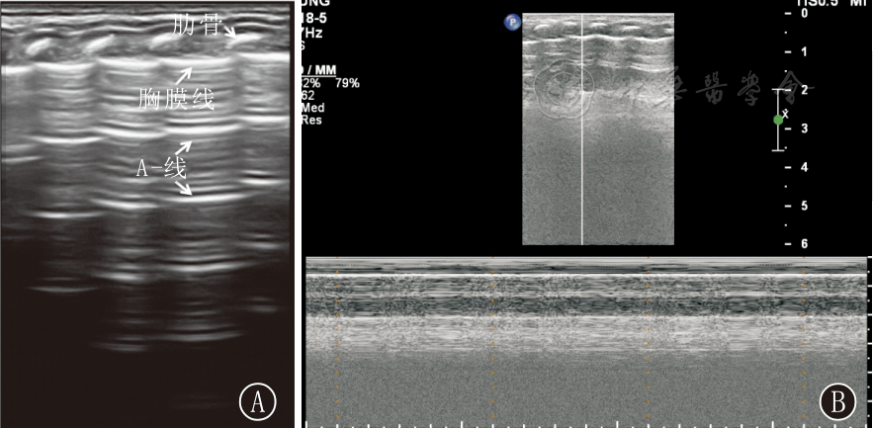

气胸

气胸在二维超声上表现为胸膜滑动征及 B 线消失,胸膜线变为带状低回声,混响伪像增多。

在 M 型超声上,正常的胸膜滑动征表现为「沙滩征」,气胸时则变为「条码征」(图 3),但以「肺点征」对气胸的特异性最大,可达 100%。所谓「肺点征」是指「沙滩征」与「条码征」相互过渡的区域(图4)。

正常肺脏超声影像学特点

新生儿正常肺组织在超声下呈低回声。在B型超声下,胸膜线与A-线均呈清晰、光滑、规则的线性高回声(光滑、清晰、规则),彼此等间距平行排列,由肺野浅部入深A-线回声逐渐减弱至消失;无(出生3~7 d后)或可有少数几条B线(生后3~7 d内),但无AIS、胸腔积液和肺实变等超声征象;在实时超声下可见肺滑,在M型超声下则表现为沙滩征

胸膜线(pleural line)与肺滑(lung sliding) 胸膜线是由胸膜与肺表面声阻抗的差异所形成的强回声反射,在超声下呈光滑、清晰、规则的线性高回声;如胸膜线消失、粗糙模糊、不规则或不连续等均为异常。在实时超声下,当探头与肋骨垂直扫描时于胸膜线处可见脏层胸膜与壁层胸膜随肺脏呼吸运动而产生一种水平方向的相对滑动,称为肺滑。